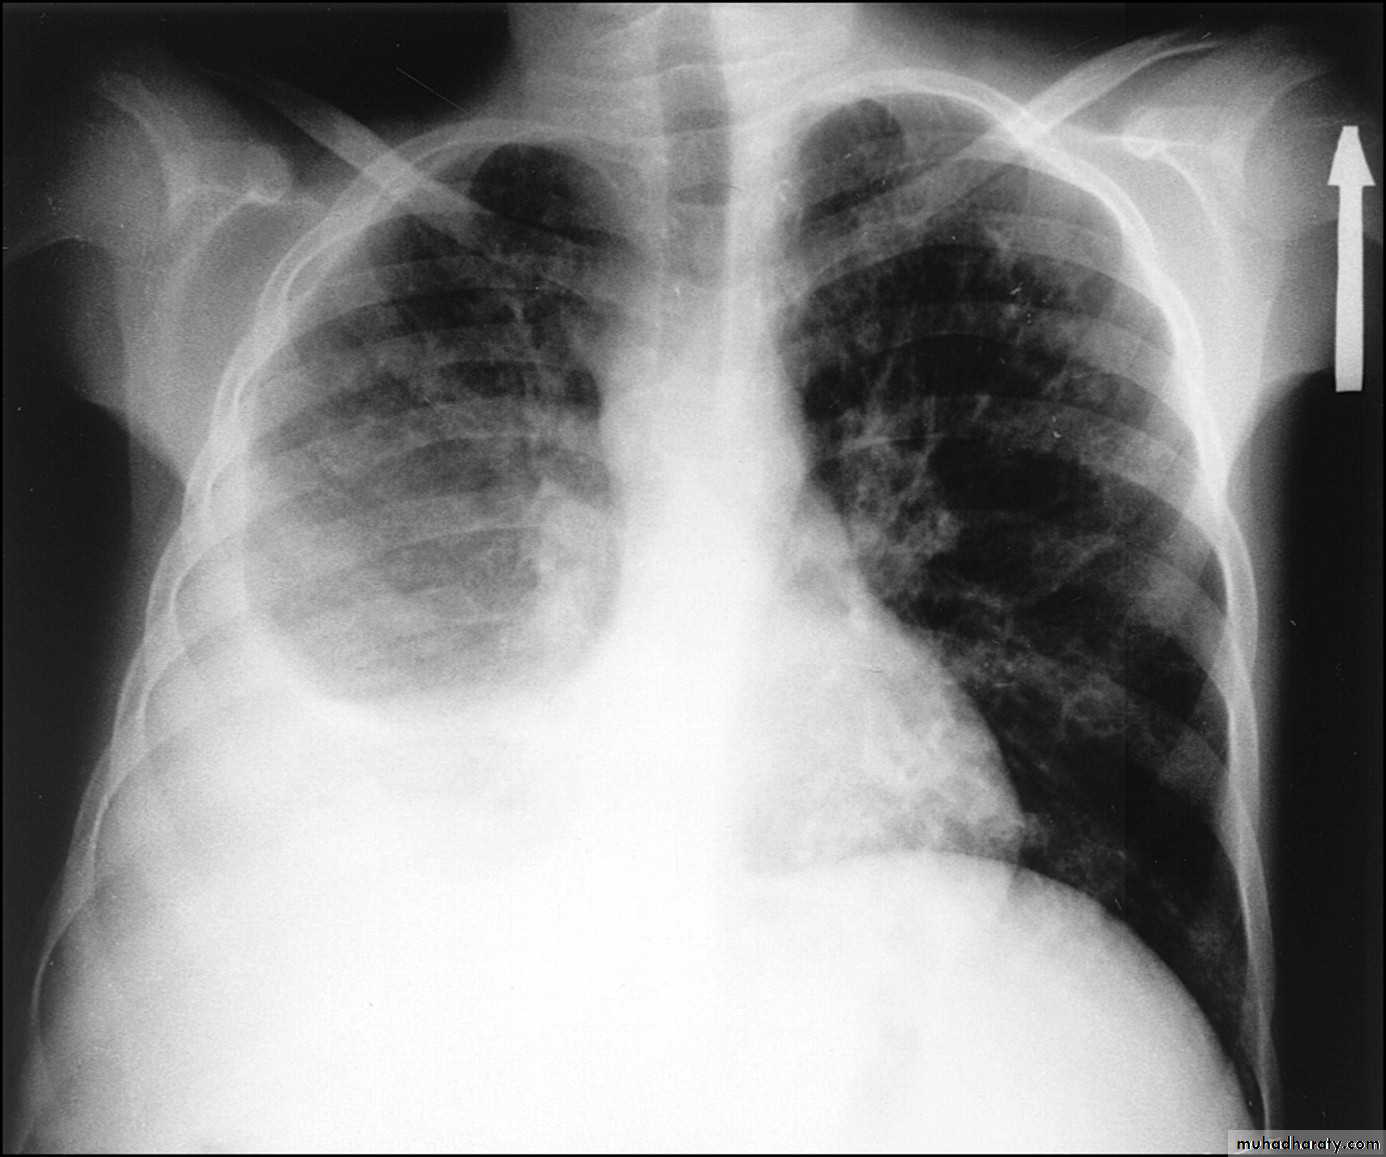

Emphysema

47.Emphyzema